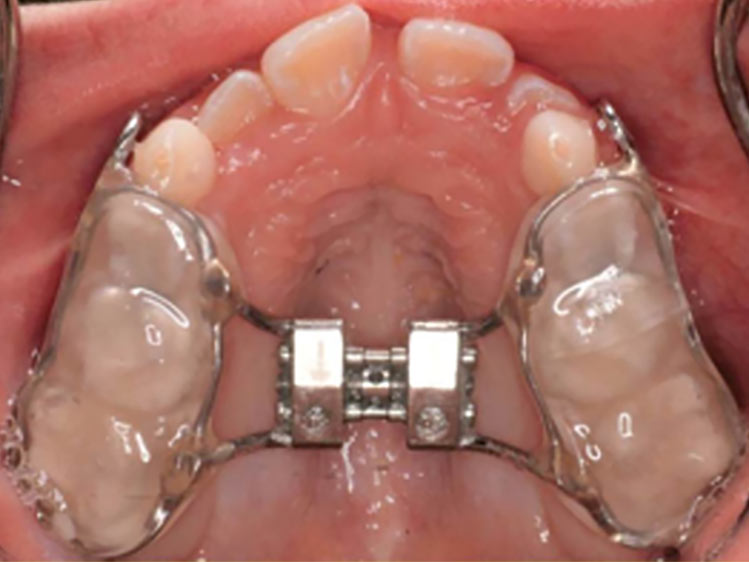

Se algo estiver fora da normalidade, o problema poderá ser interceptado e corrigido prontamente, evitando longos tratamentos ortodônticos no futuro.

As chances de correção de uma má oclusão é infinitamente maior quando é possível contar com o crescimento e desenvolvimento da criança.